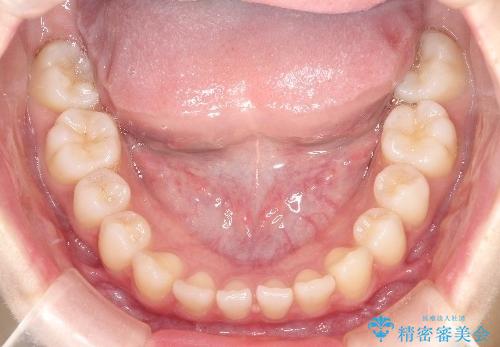

初診時の歯並びの状態としては、上下前歯が噛んでいない開口という状態であり、前歯を中心に上下とも歯の間に隙間がある状態でした。

抜歯は行わずマウスピース治療による主訴の改善を計画しました。

また、開口、スキッ歯の根本的な原因として考えられる、舌突出癖による後戻りの防止のためにMFTという舌のトレーニングも行いました。